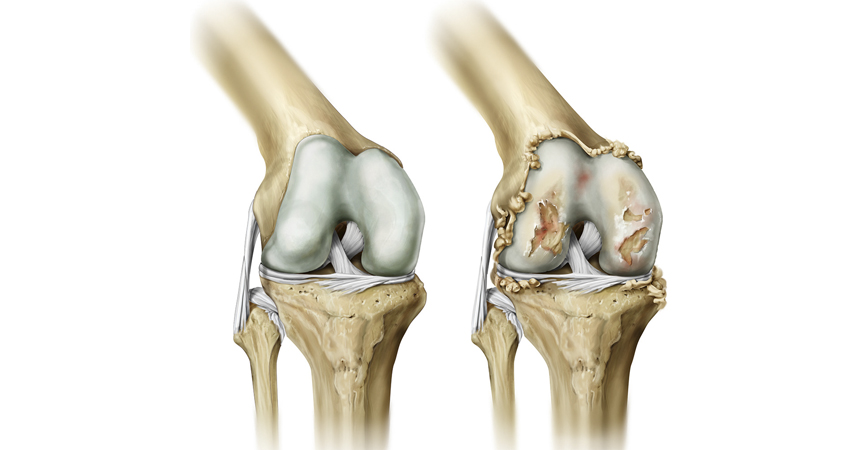

Медицинские состояния: Септический артрит коленного сустава

Раздел: Мир в картинках